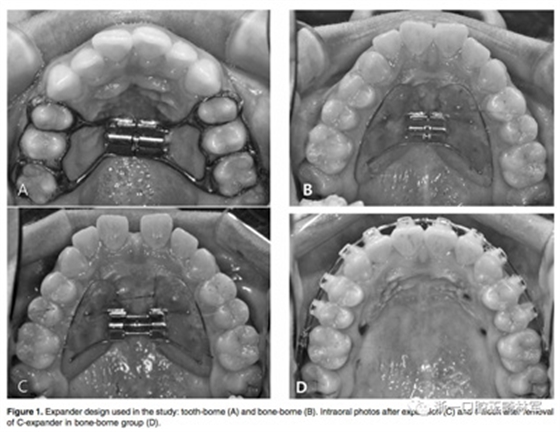

牙支持式快擴(kuò)的帶環(huán)設(shè)在第一前磨牙和第一磨牙上,見(jiàn)Figure 1A。骨支持式快擴(kuò)見(jiàn)Figure 1B-D,由直徑1.8毫米,長(zhǎng)8.5毫米的四個(gè)微種植釘支撐,兩個(gè)位于尖牙與第一前磨牙之間,另外兩個(gè)位于第二前磨牙與第一磨牙之間的腭部牙槽骨中。 每天轉(zhuǎn)動(dòng)1/4圈(0.25毫米)。